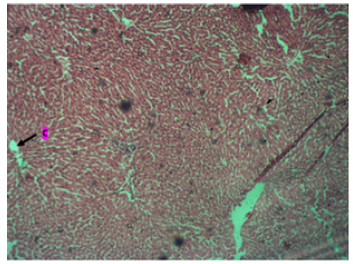

The administration of Musa Paradiasical extract at Low dose shows central vein (C). revealing many surrounding hepatocytes with sinusoids, with the parenchyma showing pseudorosettes tissue. (Plate 2).

Plate 2: Photomicrograph of the Liver in a Low Dose group with many surrounding Hepatocytes with sinusoids. Parenchyma shows Pseudorosettes tissue. Stain with H & E. X200.

The study's histology findings for the control animals display a central vein (C) and portal triad (P) with many hepatocytes with sinusoids surrounding them. As can be seen in (Plate 1), the tissue looks normal. However, in the low dose group, the central vein (C) was visible, along with many surrounding hepatocytes with sinusoids, and the parenchyma displayed pseudorosettes tissue, as can be seen in (Plate 2) above. These results are consistent with research by Olagunju, et al. (2020) [18], which found that giving plantain weed extract reduced several markers of inflammation brought on by liver injury. On the other hand, the results of administering a high dose of aqueous extract from Musa Paradiasica reveal a central vein (C) surrounded by many hepatocytes with sinusoids. Additionally, as Plate 3 illustrates, the tissue looks normal. This finding is consistent with Redoy, et al.'s [18] research from 2021, which found that plantain weed extract significantly reduced inflammation and liver enzymes to prevent liver damage.